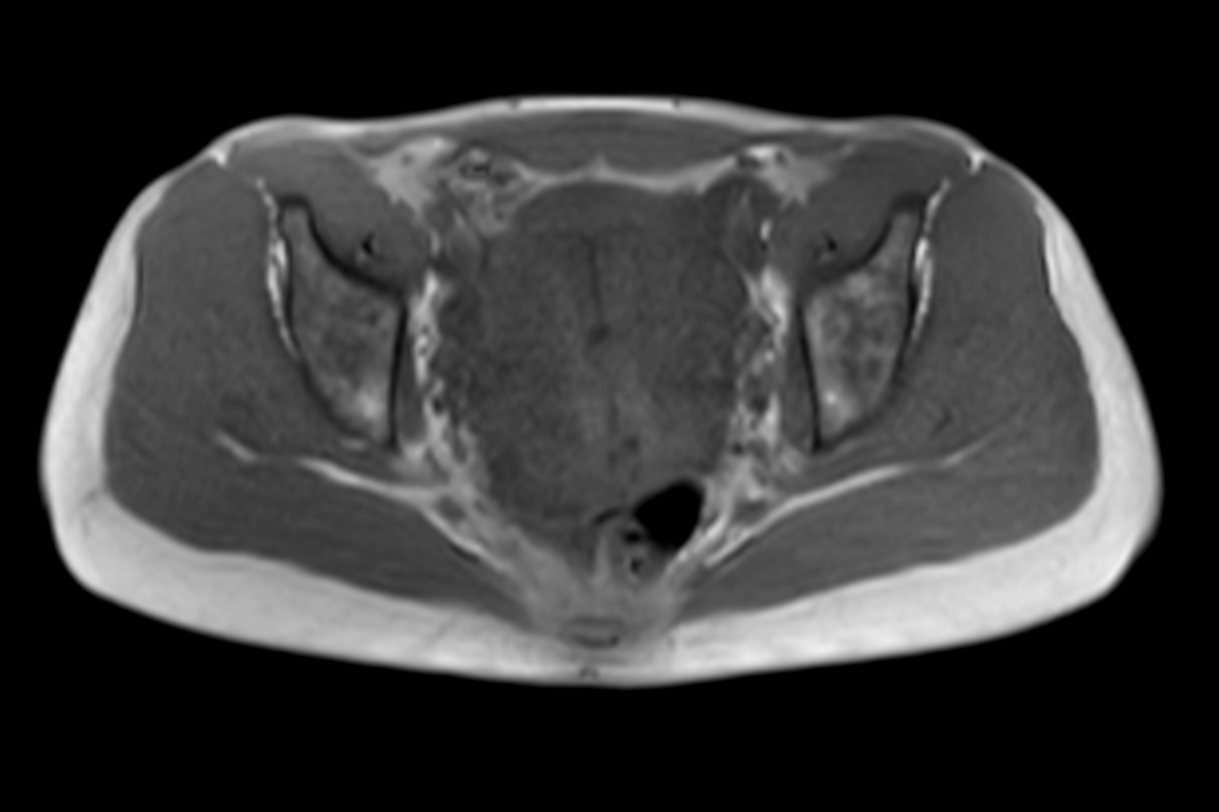

Axial MultiVane XD - T2w SPIR